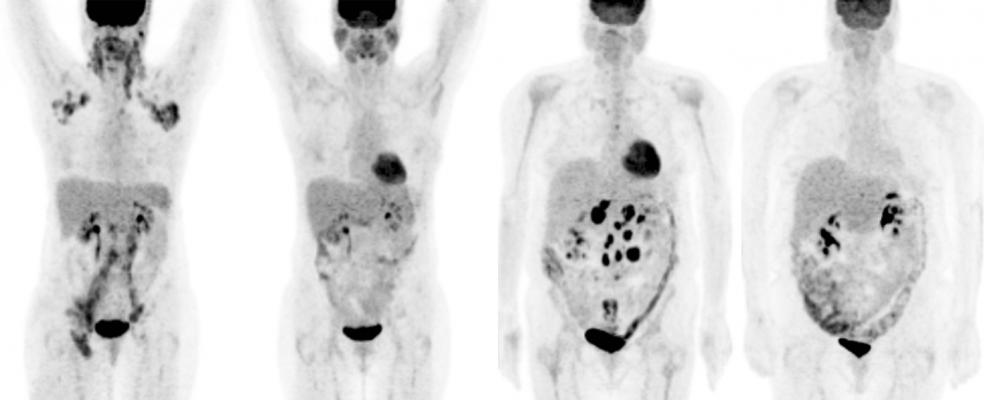

Serial F Fdg Pet Ct Scans Showing Complete Resolution Of Fdg Activity Download Scientific Diagram

Sixty Nine Year Old Male With Metastatic Pca On Androgen Deprivation Download Scientific Diagram